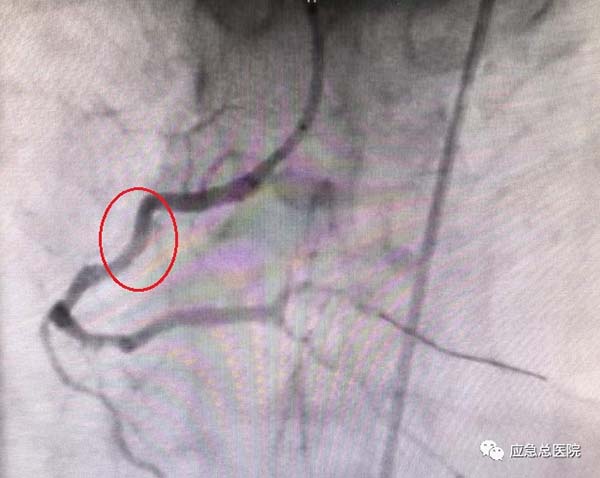

介入手术前

考虑到患者基础病多,病情复杂,治疗棘手,经过综合分析研判后,导管室范煜东主任率团队为患者实施手术。

曹大夫与患者留影

40分钟后,成功为患者植入两枚冠脉支架,迅速开通了冠脉循环,挽救了患者的心肌,为其康复后顺利出院奠定了坚实的基础。其精湛的医术、认真负责的精神、及时的救治,让患者和家人由衷称赞。于是便出现了文中开头的一幕。